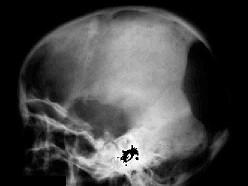

问题 男,6岁,尿量明显增多伴眼球突出1年,结合图像作出最可能的诊断?(?)

选项 A.骨髓瘤 B.转移瘤 C.白血病 D.淋巴瘤 E.Langerhans组织细胞增生症

答案 E